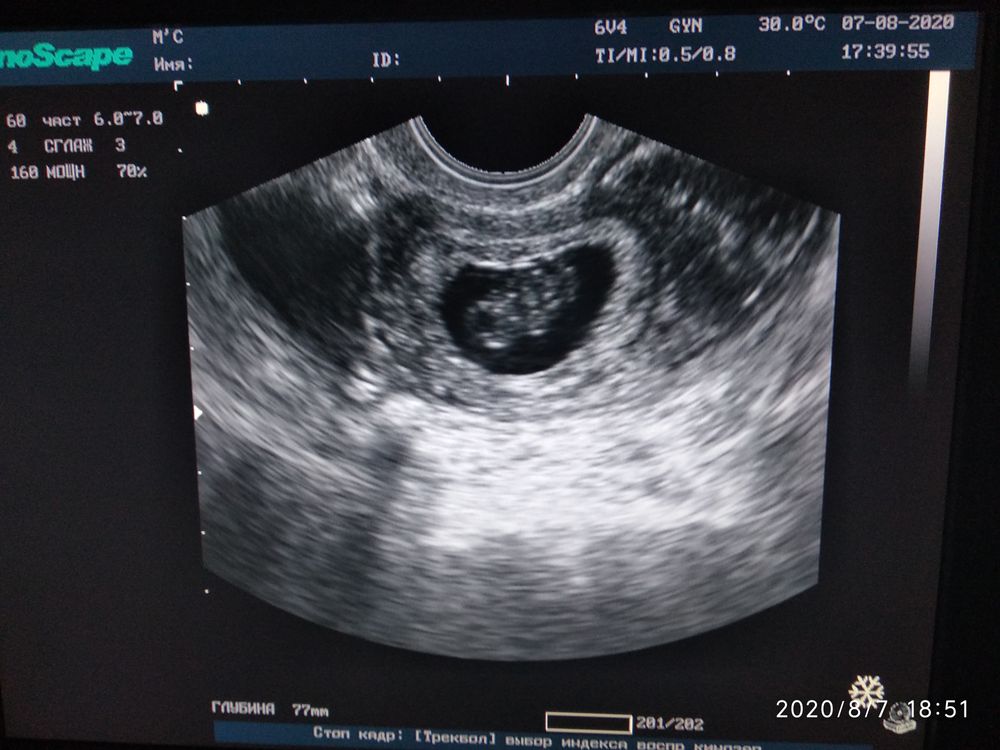

УЗИ 9 недель

УЗИ, КТГ, доплерОчень уж я нервничала, все ли хорошо с малышом и решили с мужем не мучиться и сходить ещё раз на УЗИ. Малыш растет хорошо, КТР 22 мм, на 8 недель 6 дней отставание 1 день от срока, но это ерунда, с учётом что цикл длинный. ( 7 недель 1 день было КТР 6 мм, почти недельку отставали). Сердцебиение 170 ударов. Есть крошечная гематома, но врач сказала, что даже внимания обращать на нее не будем. Что огорчило, так это тонус сильный ( поставили угрозу ), сказала что полечиться и все будет хорошо. Назначила Утрожестан, папаверин и магне в6, ну и половой покой на 2 недели пока.